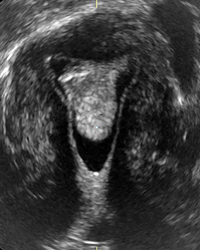

Myelomeningocele high resolution ultrasound.